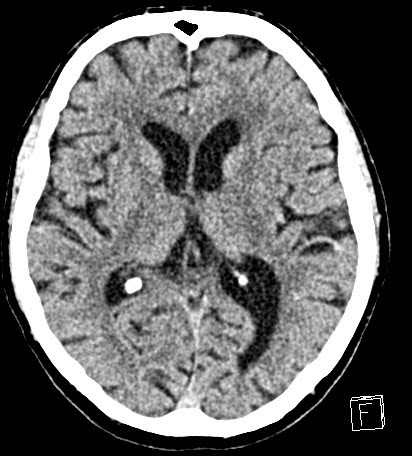

| hyperdens media sign of the M3 (opercular segment) |

| mild hypodensity according to the supplied territory (retrospective finding) |